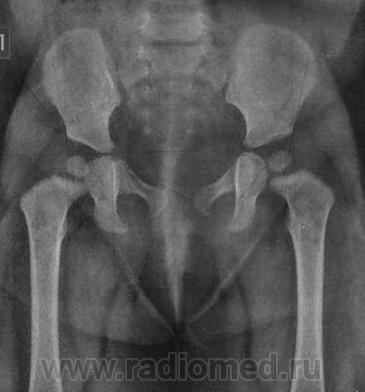

Это снимки моей дочери. На тот момент ей было 9,5 мес.

Объясните мне, пожалуйста, почему нам ставят диагонз дисплазия т/б суставов? Я не могу понять!

Заключение по этому снимку было таково:

-правая половина таза умеренно приподнята;

-ядра окостенения головок бедренных костей расположены в проекции ацетабулярной впадины, симметричны;

-ацетабулярный угол D=29гр, S=23гр;

-расстояние от центра вращения головок бедренных костей до линии Хильгенрейнера (h) D=S=10мм;

-угол наклона плоскости входа во впадину D=35гр, S=40гр;

-угол Виберга D=9гр, S=12гр;

-линии Шентона и Кальве не нарушены;

-симптом Омбреданна отрицательный с обеих сторон.

Заключение: На момент исследования определяются Rg-признаки дисплазии правого тазобедренного сустава.

думаю дело в укладке, а диагноза этого не бойтесь... вам же опрерироваться или какие то таблетки не предлагают.. а дисплазия это отклонение от официальной нормы, так сказать определенная группа риска, дажен не риска, а особого внимания...

Это норма.. извините за эмоции.